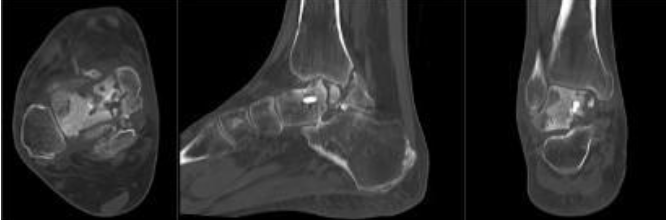

Physical examination revealed visible deformity of the ankle, including hindfoot varus and cavus with severely limited ankle joint range of motion and minimal subtalar joint motion compared to the contralateral limb. Pain and functional status were assessed using the Visual Analog Scale (VAS) and American Orthopaedic Foot and Ankle Society (AOFAS) scores pre and postoperatively. Radiographs obtained during follow-up showed collapse of the talus. A computed tomography scan performed subsequently demonstrated union of the medial and lateral malleoli, with non-union of the talus and sclerosis of the talar dome consistent with AVN (Fig. 2).

Figure 2: Pre-operative computed tomography images obtained immediately prior to revision surgery showing non-union of the talus with sclerosis of the talar dome consistent with avascular necrosis, while the medial and lateral malleoli demonstrate union.